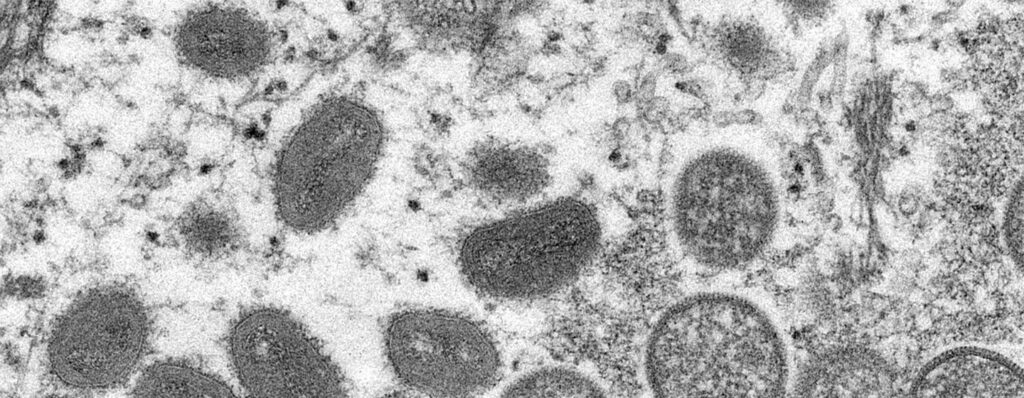

OMS publica directrices de manejo clínico para Ébola, Marburgo y otros filovirus

El ébola y la enfermedad de Marburgo, a la que también se dirigen las recomendaciones de la OMS, son graves y a menudo mortales, con tasas de letalidad que oscilan entre el 25 y el 90% en los brotes más severos

Emite Salud aviso preventivo de viaje tras brote de ébola declarado por la OMS

Entre los síntomas de la enfermedad están la fiebre, debilidad intensa, cefalea, dolor muscular, vómito, diarrea, dolor abdominal y/o sangrado inexplicable.